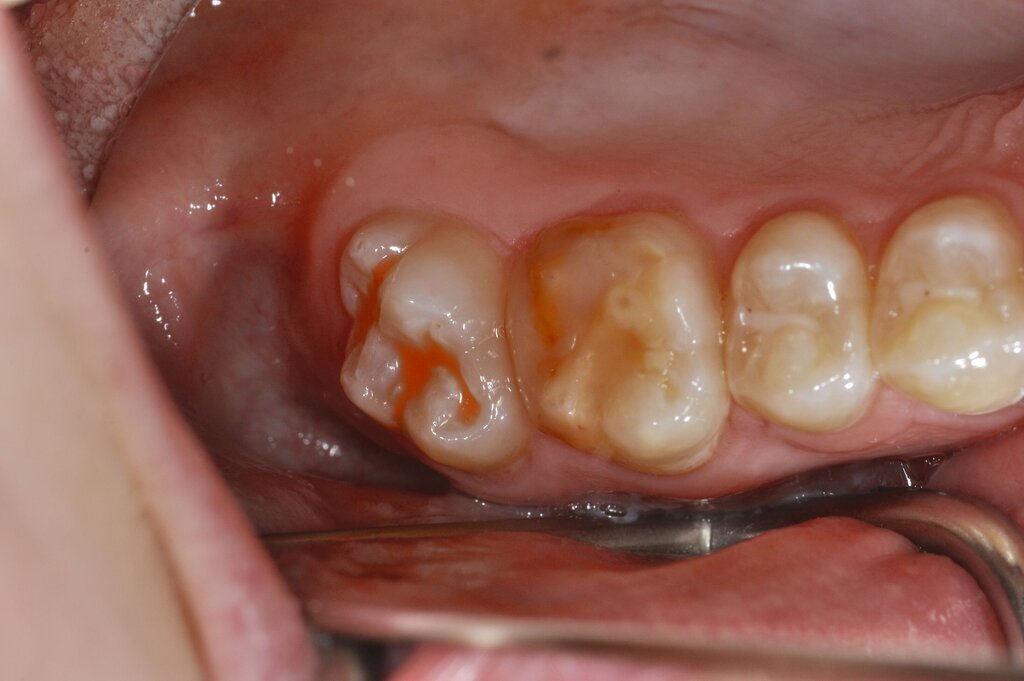

Der Vorteil der Methode ist, dass die betroffenen Zähne auch ohne Lokalanästhesie und Präparation versorgt werden können. Die temporäre Versorgung ermöglicht es, die Patienten an die zahnärztliche Behandlung zu gewöhnen. Häufig führt diese temporäre Versorgung auch zu einer Reduktion der Hypersensitivität der MIH-Zähne. Nachteil der GIZ-Versorgung ist das Risiko einer Füllungsfraktur oder eines vollständigen Verlusts der Füllung (Abbildung 4). Aktuelle Erhebungen bestätigen eine Erfolgsrate von über 80 Prozent nach einem bis zwei Jahren [Durmus et al., 2021; Mahfouz et al., 2025].

Der Behandlungsfall (Abbildung 4d) veranschaulicht die Schwächen des Verfahrens. Wird das Angebot der regelmäßigen Kontrollen nicht wahrgenommen, so droht bei Verlust der Füllung die Kariesprogression. In dem vorliegenden Fall konnte jedoch eine endodontische Maßnahme vermieden und durch die selektive Kariesentfernung die Zahnhartsubstanz weitestgehend erhalten werden.